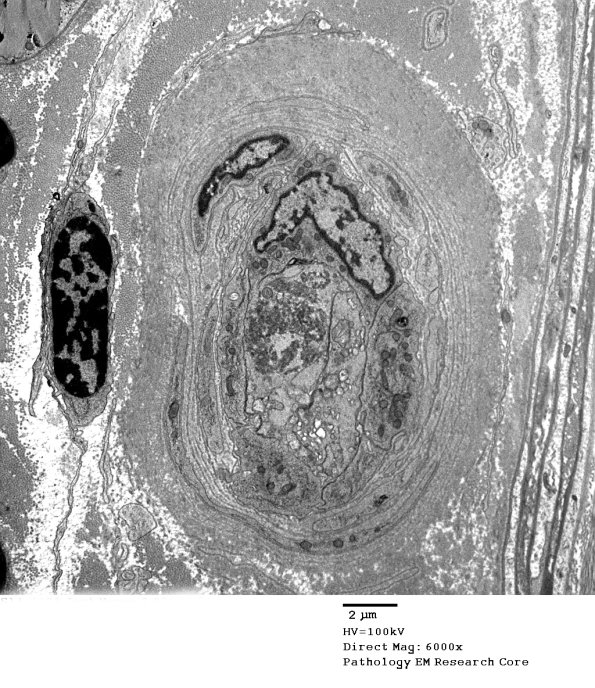

Findings consistent with plump, reactive endothelial cells in vessels with thickened collagenized walls. (electron micrographs)